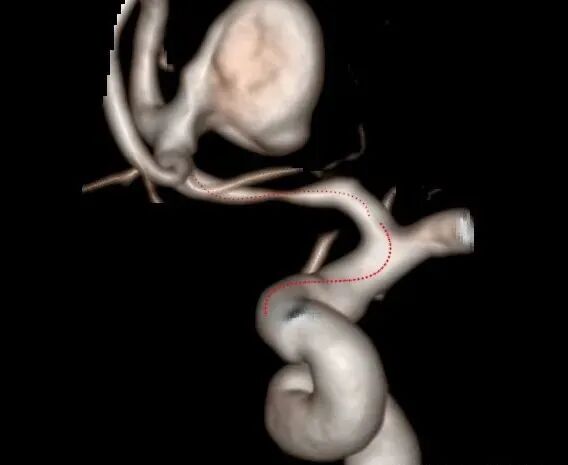

上面这图在塑形针的头端用手按压一下,是塑折角的弯,用来做闭塞血管的开通。

分支一主支血管角度越大,导丝头端的弯曲度越大,主支一血管直径越大,导丝前端弯曲部分也越长。

从上面的图片可以看出来,同一个血管分支我们可以采用不用的塑形形态,术者要有一定的空间想像能力和操纵导丝的技术去实现目的。